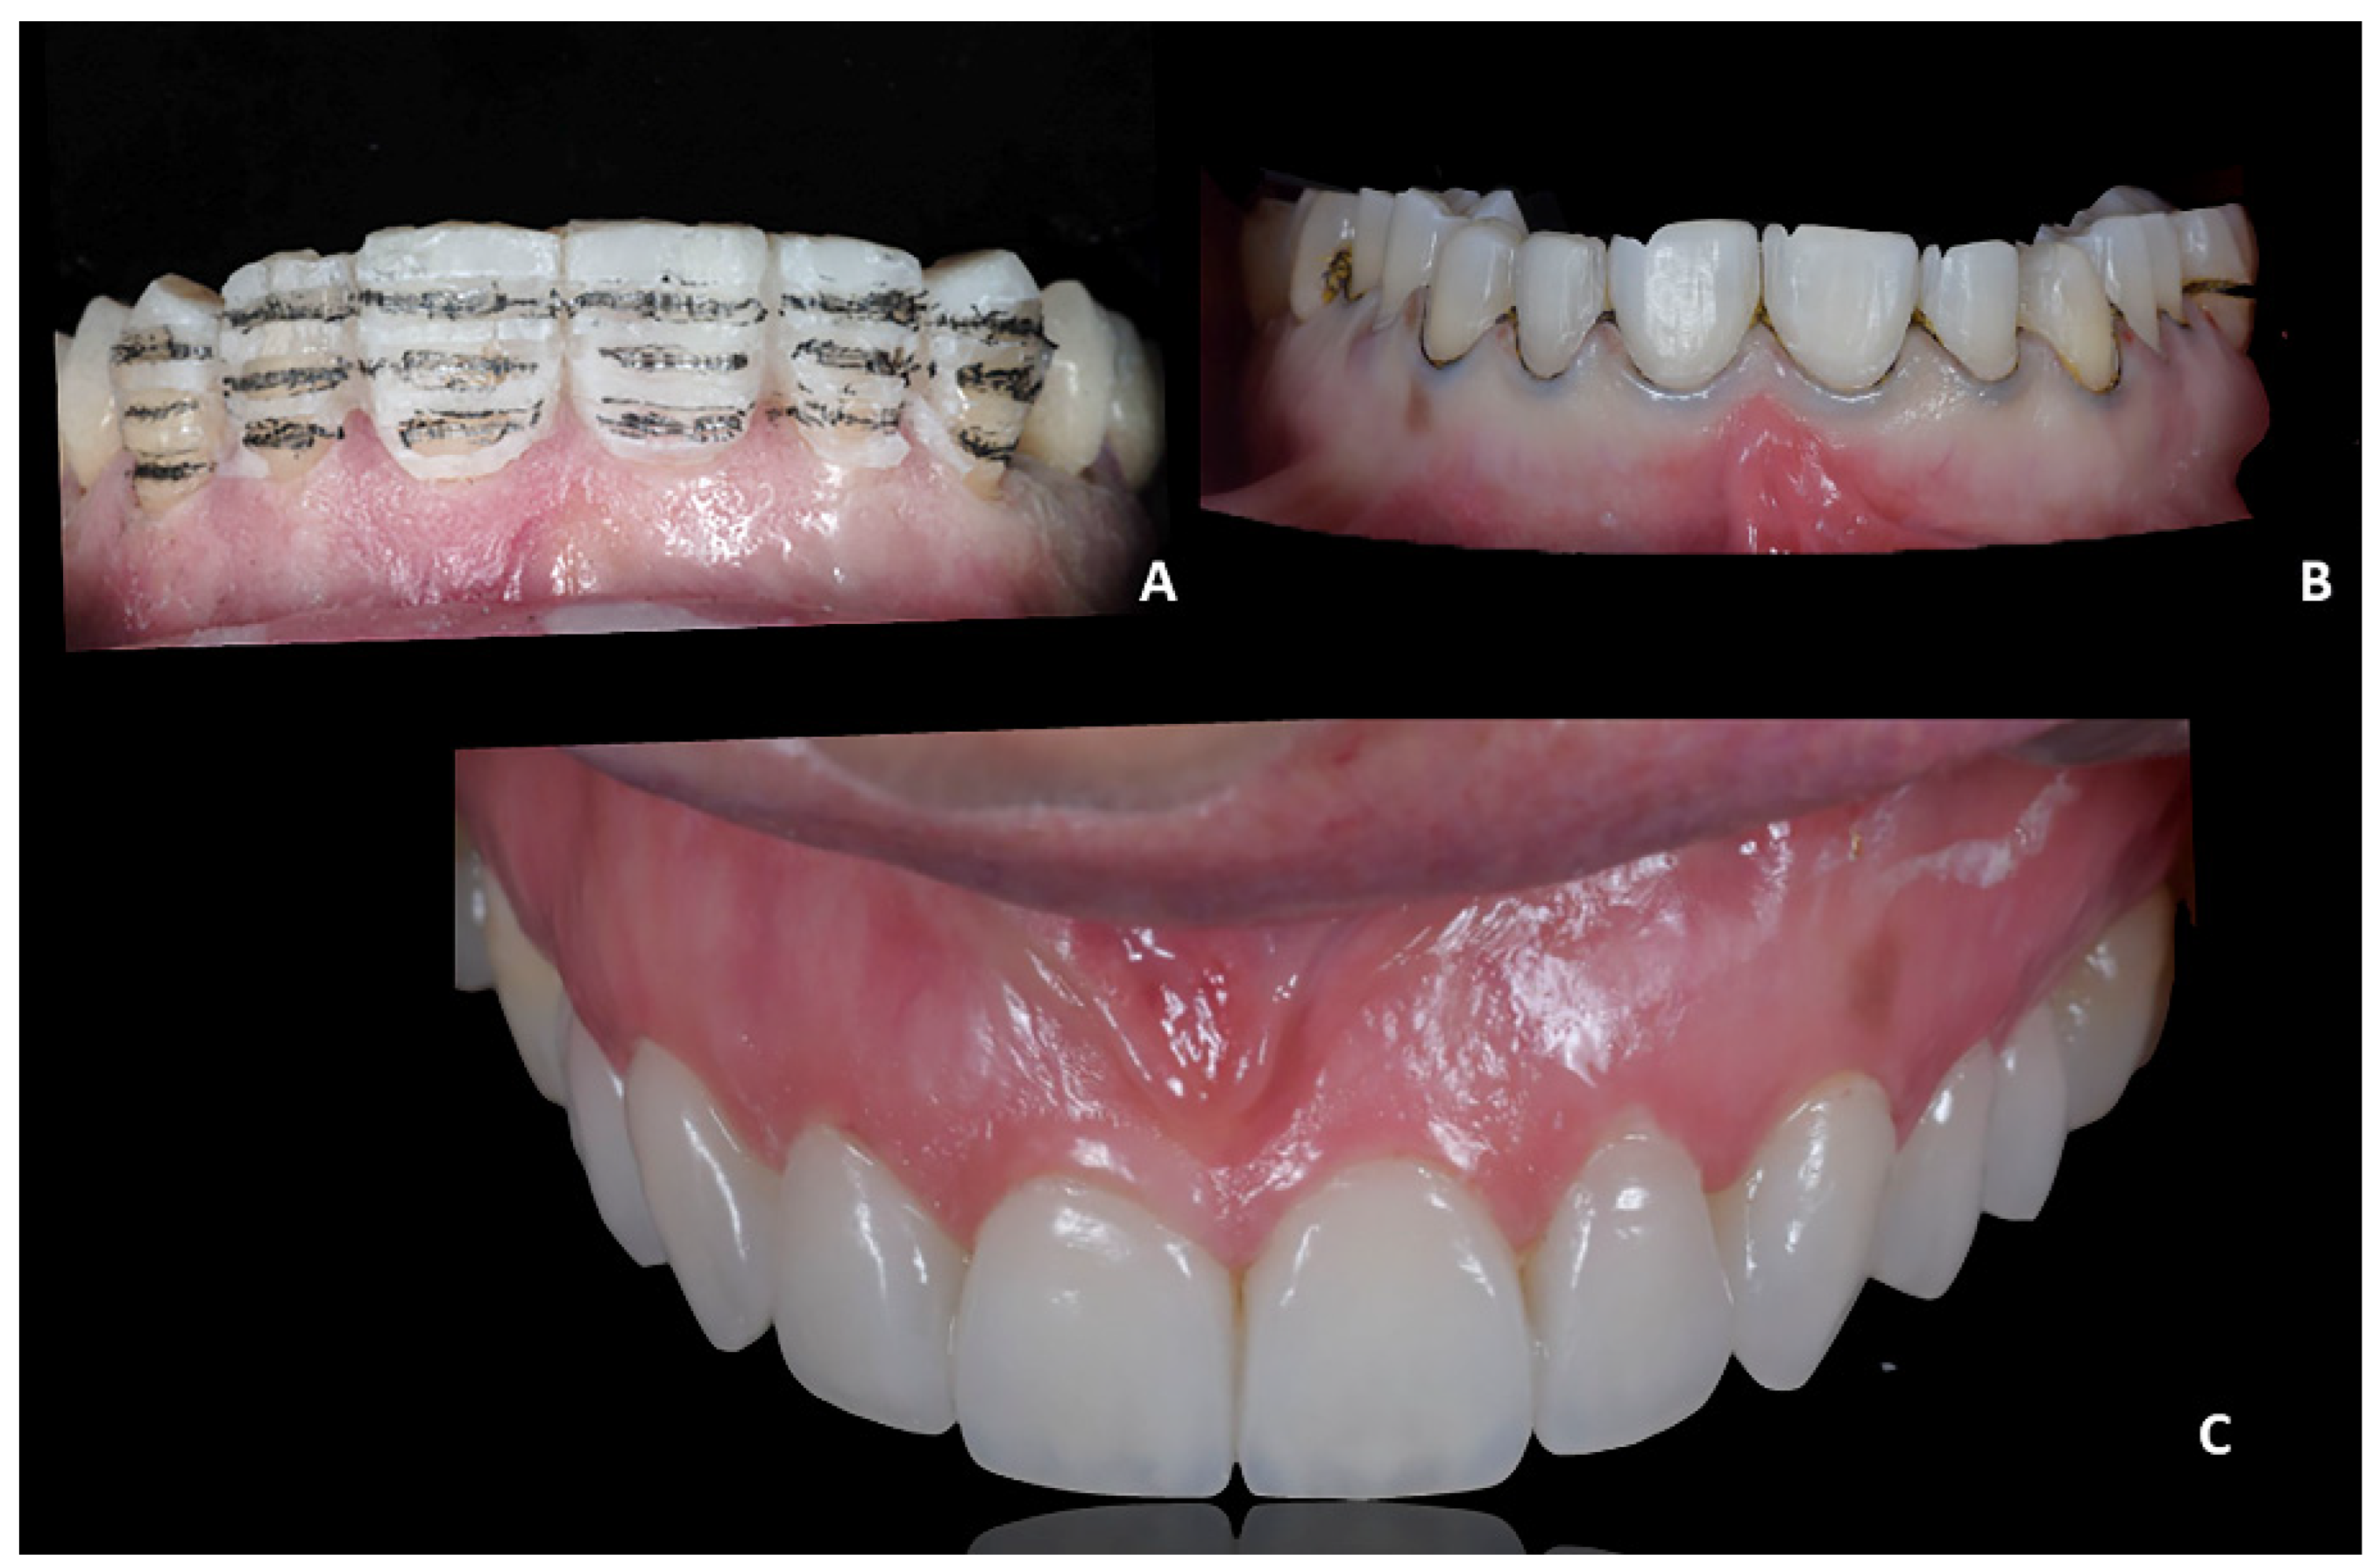

Figure 5. Case 1. (A) Pre-treatment composite mock-up; (B) dental alignment after orthodontic treatment; (C) final mock-up.

Orthodontic treatment. Orthodontic movements were programmed according to the final prosthetic rehabilitations, following the principle of PGO. In this regard, the Invisalign GO system achieved predictable results with the maximum satisfaction of both the patient and the doctor (Figure 5B). The programmed orthodontic movement was staged, and eight aligners were required to achieve the final pre-prosthetic teeth position. Each aligner was worn for two weeks for a total treatment time of 4 months.

After orthodontic treatment, an intra-oral scan was performed to register the final position of the teeth. A new silicon key was produced to apply the final mock-up, which would serve as a customized guide to set the depth of the tooth preparation for the application of veneers (Figure 5C). Additionally, the authors found that the validation mock-up (i.e., the mock-up generated from the orthodontic set-up and used for the pre-visualization of the outcomes) fit perfectly after the orthodontic treatment, confirming that the programmed orthodontic movement with CAT was predictable, especially for minor corrections as those required in the prosthetic conformative approach. In light of this clinical experience, it could be postulated that clinicians may even use the pre-visualization silicone key for generating the final mock-up; however, in the absence of solid scientific evidence, the authors suggest evaluating this approach on a single-case base.

Generation of the mock-up and validation of the project. According to the digital project, the diagnostic wax-up was prototyped, and the silicon key for the intra-oral mock-up was generated (Figure 5A). The authors recommend using a rigid laboratory silicone (platinum 85—Zhermack). The silicon key was filled with a self-hardening composite material with high aesthetic performance; in this case, we used the composite Acrytemp A2 (Zhermack). The mock-up clinical test represents a critical stage in the rehabilitation process since the mock-up enhances the communication with the patient showing a realistic preview of the final aesthetic rehabilitation and providing clinicians with a better understanding of the patient’s aesthetic expectations [9,10]. As a consequence, the patient’s satisfaction with the treatment strictly depends on the consistency of the final product with the mock-up [11,12]. Finally, this stage is important to clinically test and validate the functional adaptability of the prosthetic project.